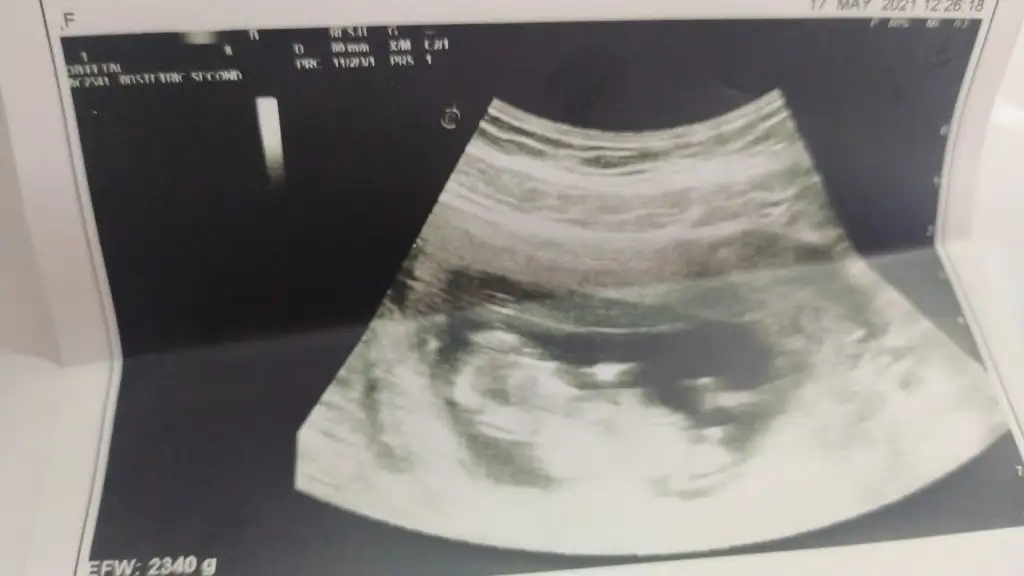

Erkek görünüyorbenim usg leri de yorumlayabilir misiniz acaba![]()

Peki kesin midir değişir mi sonradan bu hafta eşime sürpriz yapmayı düşünüyorumdaKız görünüyor![]()

Tahminim kız ama yinede Dr bekleyinPeki kesin midir değişir mi sonradan bu hafta eşime sürpriz yapmayı düşünüyorumda